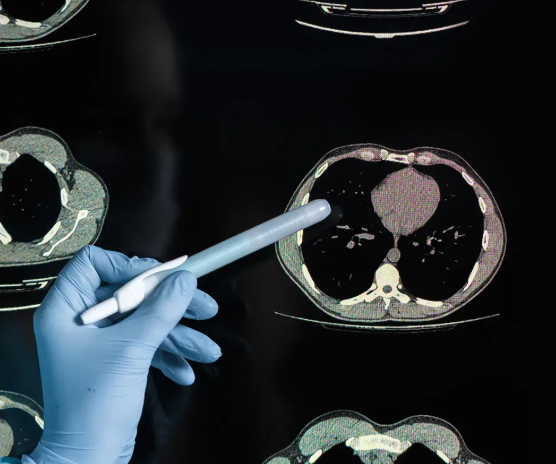

조영제 사용과 촬영 전후 주의사항

흉부CT는 조영제를 사용하지 않는 ‘단순 CT’와, 혈관·장기 구분을 위해 조영제를 사용하는 ‘조영 CT’로 나뉩니다. 조영제는 정맥으로 주입되며, 혈류를 따라 이동하면서 특정 부위의 명암을 더 뚜렷하게 만듭니다. 하지만 알레르기 반응이나 신장 기능 저하가 있는 경우 주의가 필요하므로, 이전 경험이나 약물 알레르기를 반드시 의료진에게 알려야 합니다.

촬영 전 준비

조영제를 사용할 때는 보통 4시간 정도 금식이 필요합니다. 금속 장신구, 브래지어의 와이어, 의류의 지퍼 등은 영상에 영향을 주므로 모두 제거합니다. 또한 검사 중에는 숨을 잠시 멈추라는 안내가 있을 수 있으므로, 검사 전에 호흡을 편안히 하는 것이 도움이 됩니다.

촬영 후 관리

조영제를 사용한 경우, 검사 후에는 수분을 충분히 섭취하여 몸 밖으로 빨리 배출되도록 하는 것이 좋습니다. 가벼운 어지럼이나 몸이 따뜻해지는 느낌이 일시적으로 나타날 수 있으나 대부분 금방 사라집니다. 다만 두드러기나 구토 등 이상 증상이 있으면 반드시 병원에 연락해야 합니다.